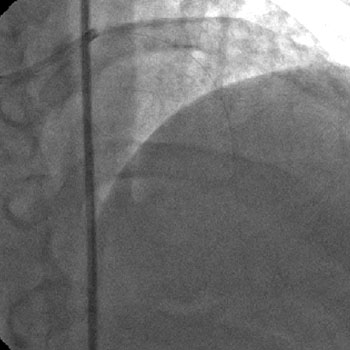

1) RCA: Discrete severe mid stenosis (Figure 1)